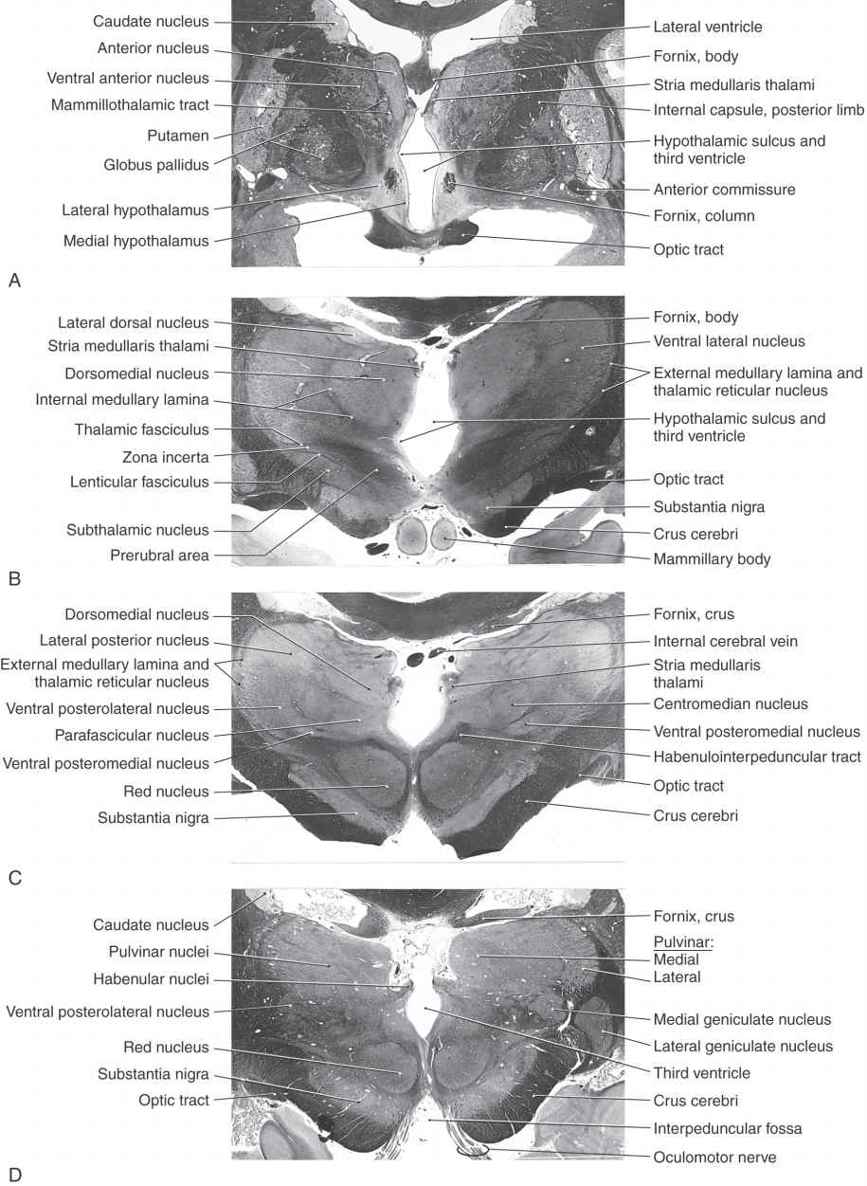

Figure 15-7. Four levels of the forebrain from rostral (A) to caudal (D) showing the internal structure of the hemisphere with emphasis on the diencephalon. These levels correlate with those shown in Figure 15-6 and with the planes represented in the exploded view in Figure 15-10. Weil stain.

All four diencephalic subdivisions can be approximated in a midsagittal section of the forebrain (Figs. 15-4 and 15-6). The dorsal thalamus is located superior to the hypothalamic sulcus and extends from the interventricular foramen caudally to the level of the splenium of the corpus callosum. The hypothalamus lies inferior to the hypothalamic sulcus and is bordered rostrally by the lamina terminalis and caudally by a line that extends from the posterior aspect of the mammillary body superiorly to intersect with the hypothalamic sulcus. The only diencephalic structures visible on the inferior surface of the hemisphere are those related to the hypothalamus, including the optic chiasm, infundibulum, medial and lateral eminences, and mammillary bodies (Fig. 15-5). The ventral thalamus (subthalamus) does not border on the ventricle; rather, it occupies a position caudal to the hypothalamus, rostral to the diencephalon-midbrain junction, and lateral to the midline (Figs. 15-4 and 15-7B). Epithalamic structures are located posteriorly and caudally, in close apposition to the posterior commissure, and include the pineal gland, the habenular nuclei, and the main afferent bundle of these nuclei, the stria medullaris thalami.

The thalamus is covered on its lateral aspect by a layer of myelinated axons, the external medullary lamina, which includes fibers that enter or leave the subcortical white matter (Fig. 15-7B, C). Within the external medullary lamina are clusters of neurons that form the thalamic reticular nucleus. The medial surface of the thalamus borders the third ventricle, and the external medullary lamina and thalamic reticular nucleus blend with the thalamic fasciculus and zona incerta, respectively, to form an interface between dorsal and ventral thalami (Fig. 15-7B).

Finally, attached to the caudolateral portion of the thalamus are the medial and lateral geniculate bodies (and their correspondingly named subjacent nuclei) (Figs. 15-7D, 15-8D, and 15-10). Although considered here as components of the lateral nuclear group, the geniculate nuclei are sometimes considered as a separate part of the thalamus, the metathalamus.

This large collection of thalamic neurons is grouped into dorsal and ventral tiers. The relatively small group of dorsal tier nuclei includes the lateral dorsal and lateral posterior nuclei along with the much larger pulvinar nucleus (pulvinar) (Figs. 15-7B-D, 15-8D, 15-9, and 15-10). The connections of the lateral dorsal and lateral posterior nuclei are formed with the cingulate gyrus and parietal lobe, respectively (Fig. 15-10). The large pulvinar nucleus consists of anterior, medial, lateral, and inferior subdivisions. The inferior division receives input from the superior colliculus and projects to the visual association cortex. Other portions of the pulvinar project to areas of the temporal, parietal, and frontal lobes that are especially concerned with visual function and eye movements (Fig. 15-11).

The large ventral tier of the lateral group consists of three separate nuclei (Figs. 15-7, 15-8B, C, and 15-9). The ventral anterior nucleus (VA) and the slightly more caudal ventral lateral nucleus (VL) are important motor-related nuclei; the ventral posterior nucleus, consisting of ventral posterolateral (VPL) and ventral posteromedial (VPM) nuclei, convey somatosensory information to the cerebral cortex.